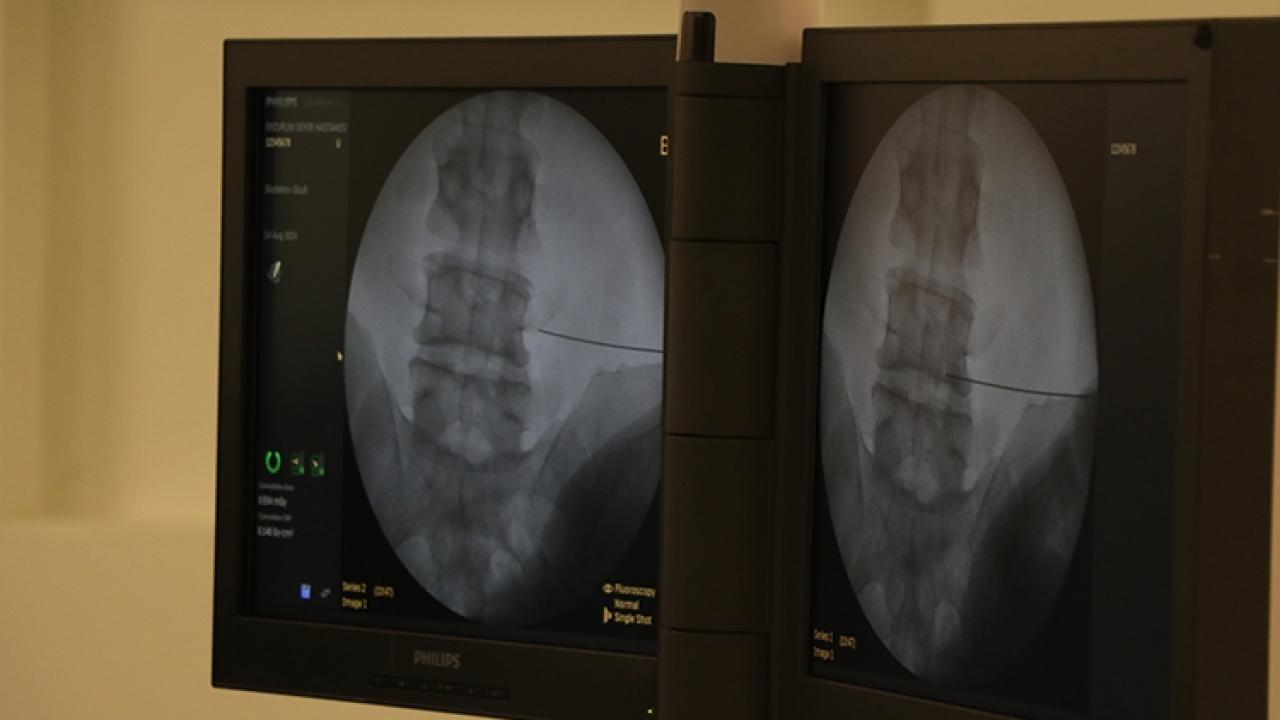

"Günümüzde fıtık ameliyatlarının açık ve laparoskopik (kapalı) yöntemlerle başarıyla uygulanıyor. Cerrahi yöntem hastaya özel olarak planlanıyor. Günümüzde fıtık ameliyatları son derece güvenlidir. Buna karşın fıtıkla uzun süre yaşamak ciddi riskler barındırır. Doğru bilgi, doğru zaman ve doğru tedavi hayat kurtarır."